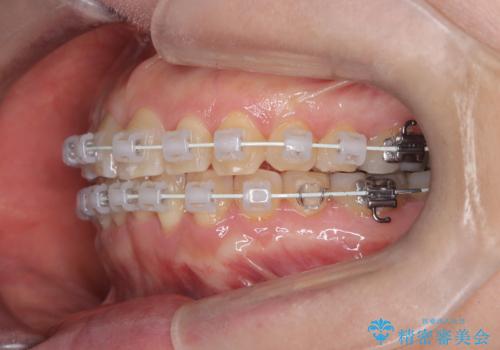

今回の矯正治療では、歯の色に近い目立たない審美ブラケットとワイヤーを使用しました。

スペース確保のために、まず奥歯全体をわずかに後方へ動かす遠心移動を実施し、前歯を並べるためのスペースを確保。さらに、安全性に配慮しながら歯の側面をわずかに削るIPRを併用し、デコボコを解消しました。

ワイヤー矯正ならではの確実な歯のコントロールにより、当初の計画通り約1年という短い期間で、前歯のガタつきが解消。見た目が美しく整っただけでなく、清掃しやすい機能的な歯並びを獲得していただけました。